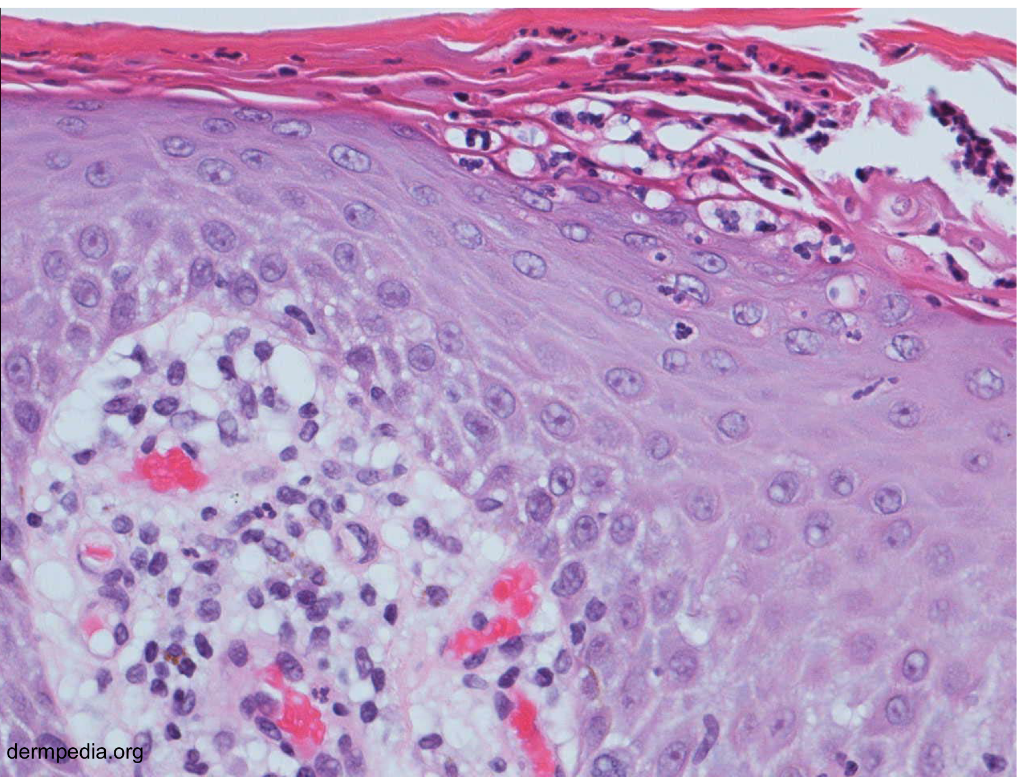

Suprabasal acantholytic blister histology

row of tombstones, intact basal cells at base of blister

pemphigus vulgaris

Acantholysis

dissolution of intercellular bridges that connect squamous epithelial cells → rounded, dissociated cells